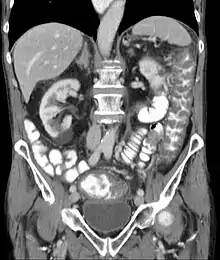

Prior to the advent of tests to detect C. difficile toxins, the diagnosis most often was made by colonoscopy or sigmoidoscopy. The appearance of "pseudomembranes" on the mucosa of the colon or rectum is highly suggestive, but not diagnostic of the condition.[45] The pseudomembranes are composed of an exudate made of inflammatory debris, white blood cells. Although colonoscopy and sigmoidoscopy are still employed, now stool testing for the presence of C. difficile toxins is frequently the first-line diagnostic approach. Usually, only two toxins are tested for—toxin A and toxin B—but the organism produces several others. This test is not 100% accurate, with a considerable false-negative rate even with repeat testing.[46]